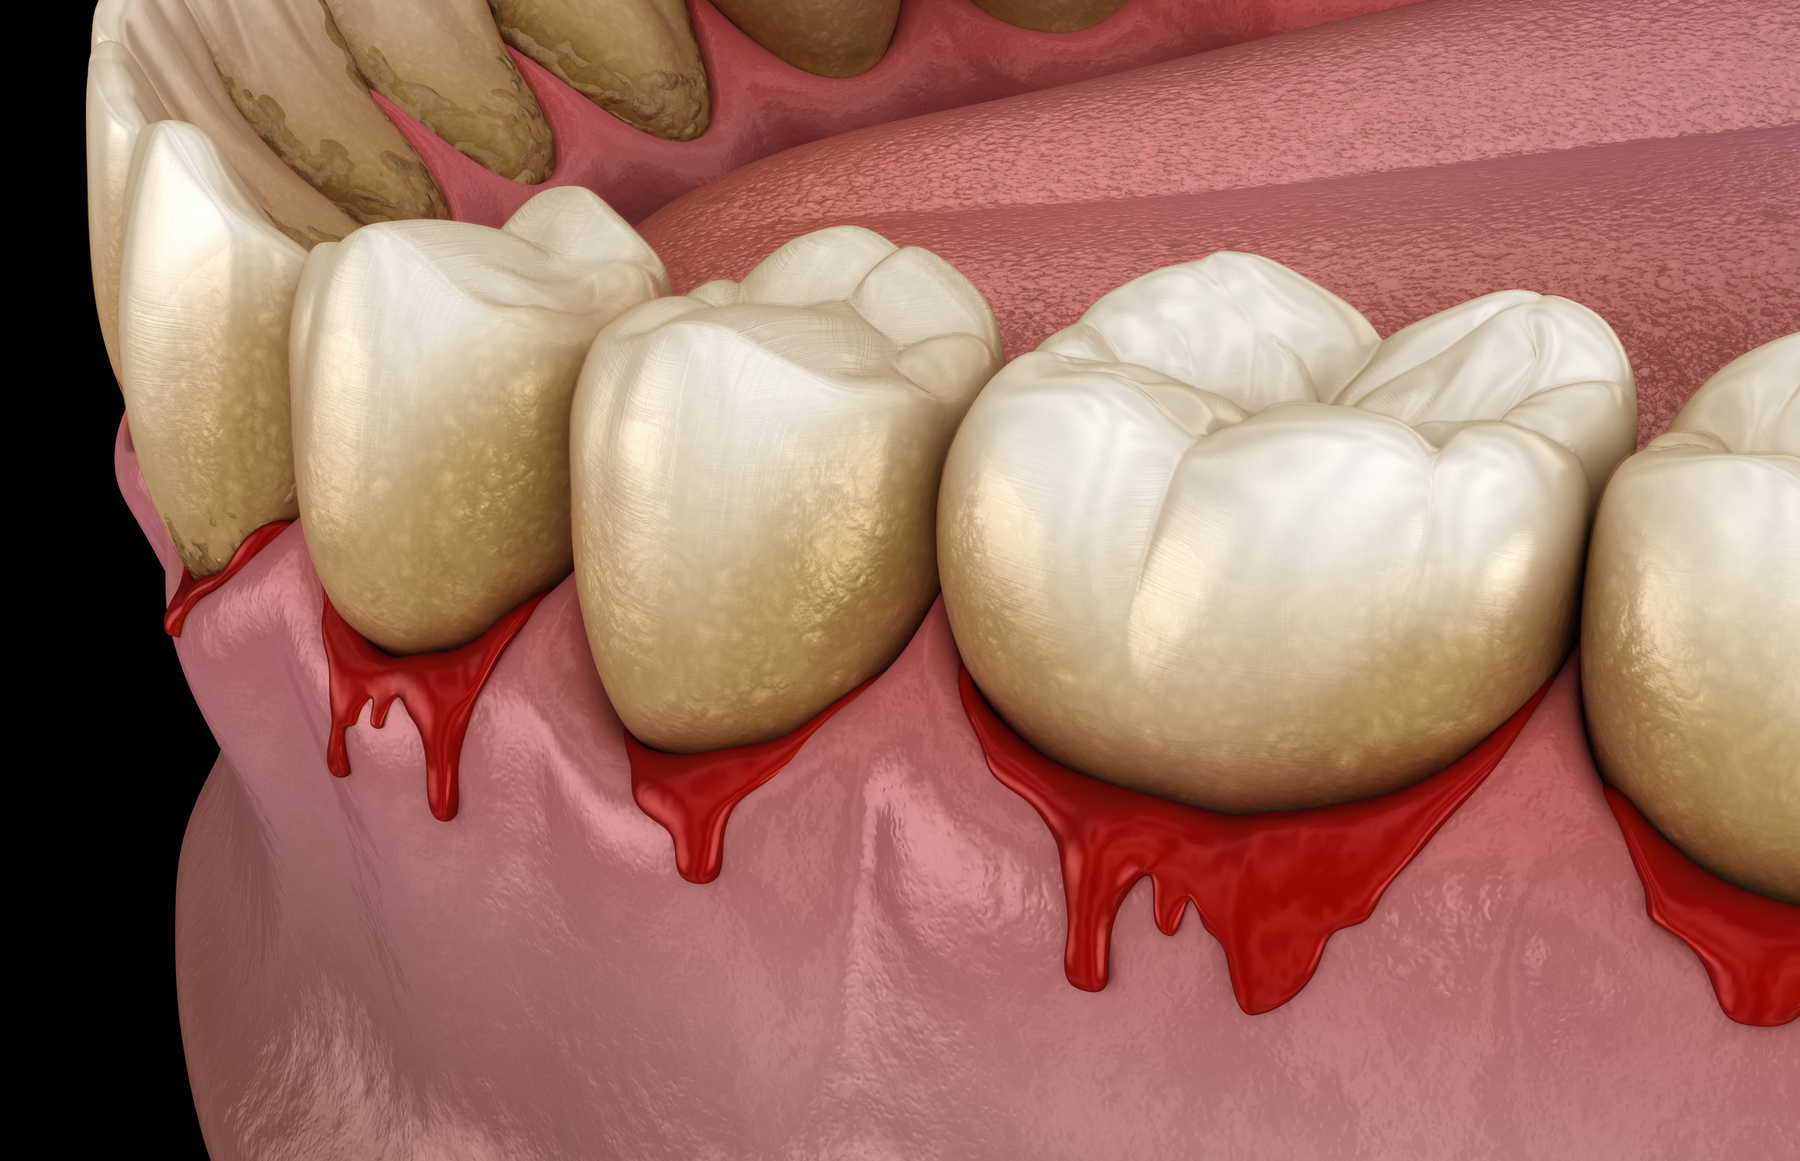

Η ουλίτιδα είναι το πρώιμο στάδιο της περιοδοντικής νόσου, με ερεθισμένα ούλα που αιμορραγούν. Είναι αναστρέψιμη με καλή στοματική υγιεινή στο σπίτι και καθαρισμό δοντιών στο κλινική.

Σε περίπτωση που παρατηρήσετε αίμα στα ούλα σας όταν βουρτσίζετε τα δόντια ή κάνετε νήμα, να γνωρίζετε πως δεν είναι φυσιολογικό ούτε υγιές.